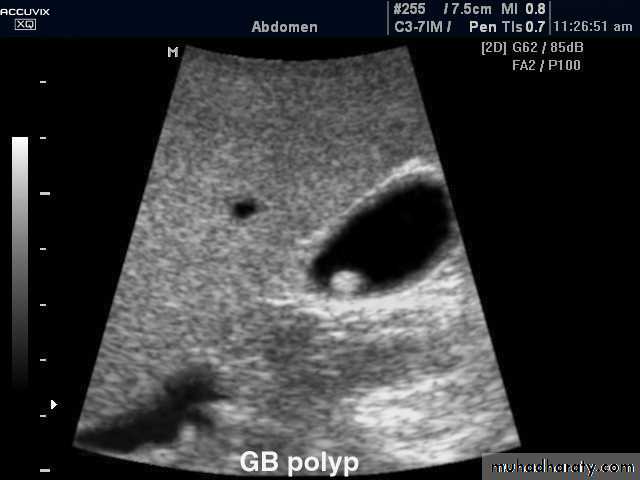

Gall bladder ,biliary tree

• no contrast.Gall stone & cholecystitis

US